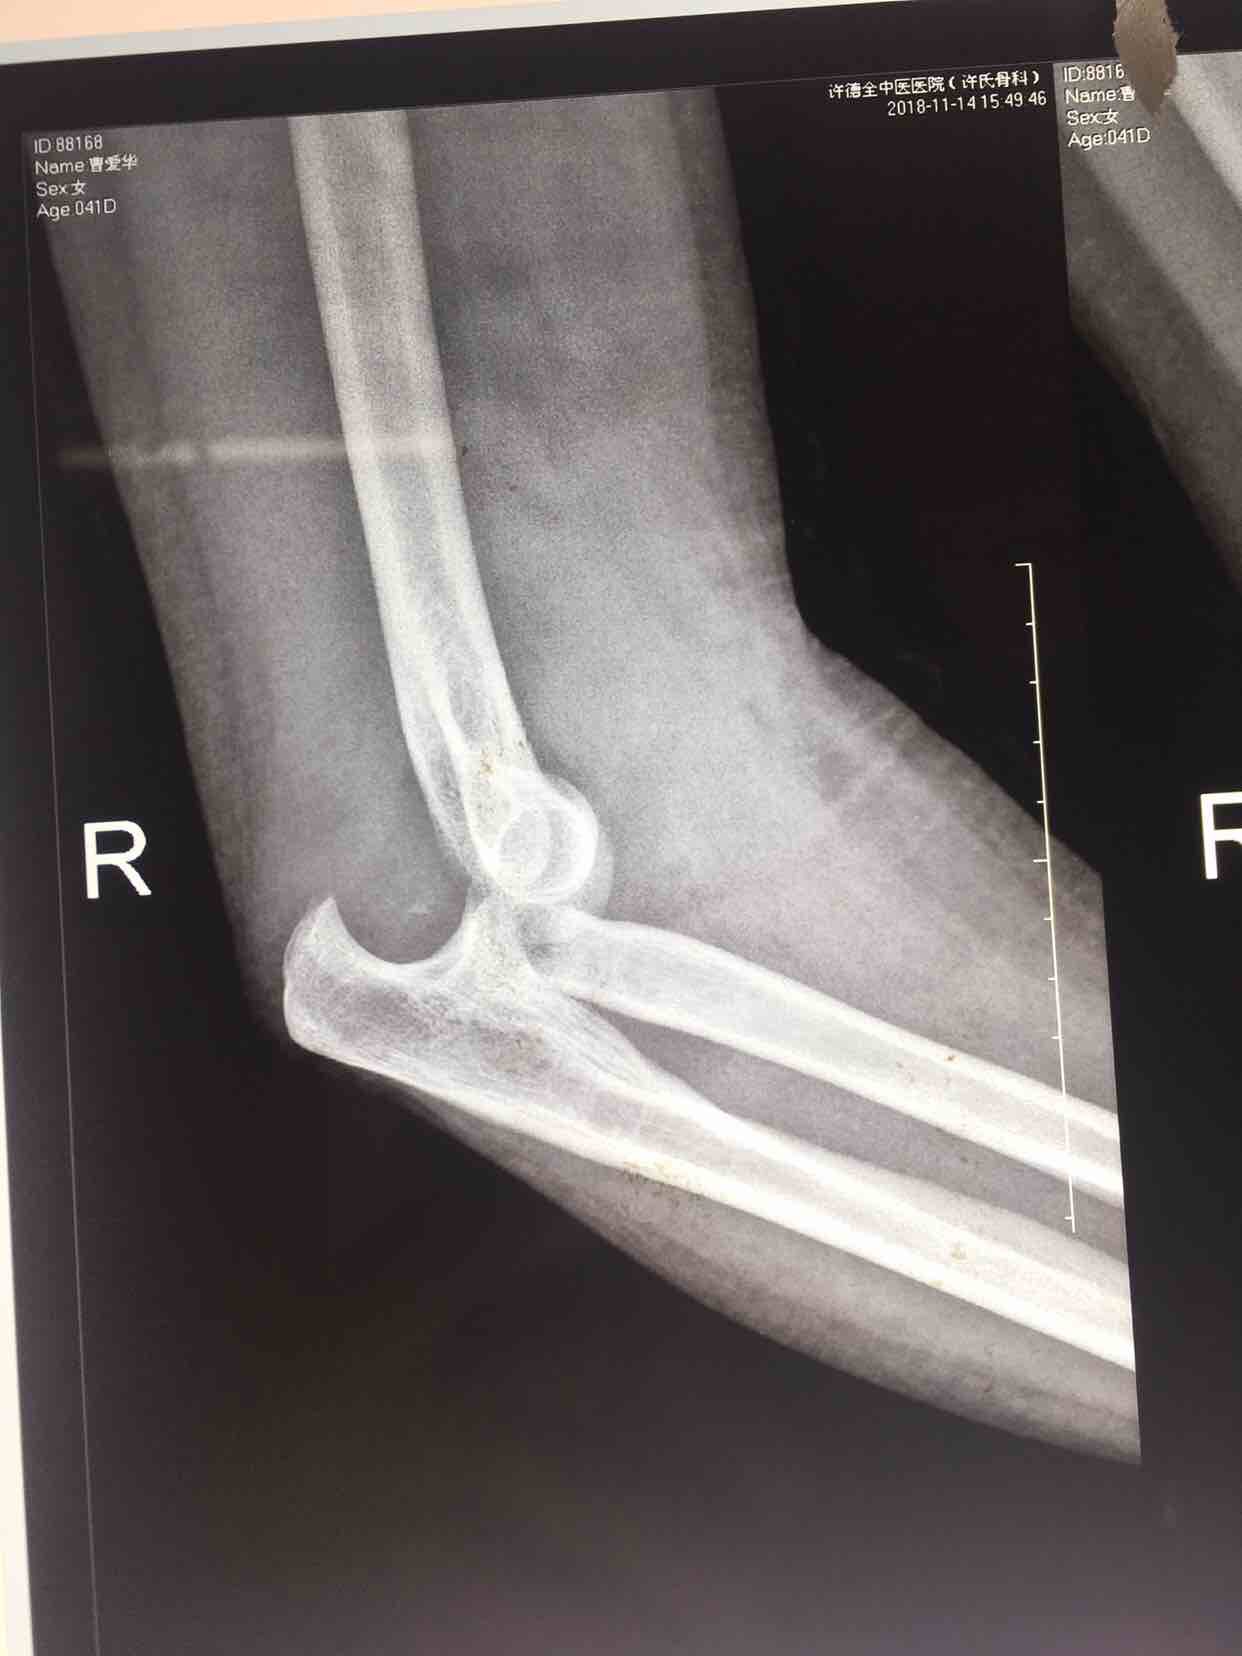

打开应用肘关节脱位合并桡骨头骨折一例

患者因外伤入院,行X线检查显示有肘关节脱位合并绕骨头骨折,遂行内固定手术。